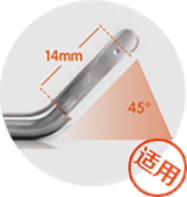

Break away from traditional treatment根据患者腋下的弧度选择适合患者最佳角度的手柄刀头量身定制祛臭专属方案。

大汗腺分布范围 较广、深度较大 的中度腋臭、多 汗型腋臭等